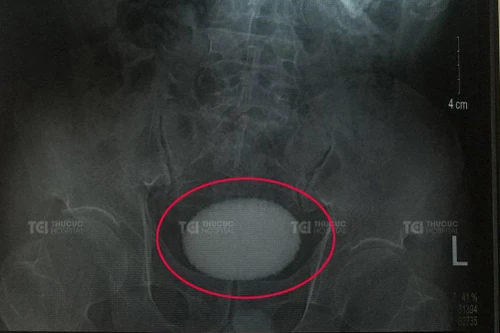

Hiếm gặp: Bóc viên sỏi kích thước khủng, to tròn như quả trứng vịt nằm trong bàng quang